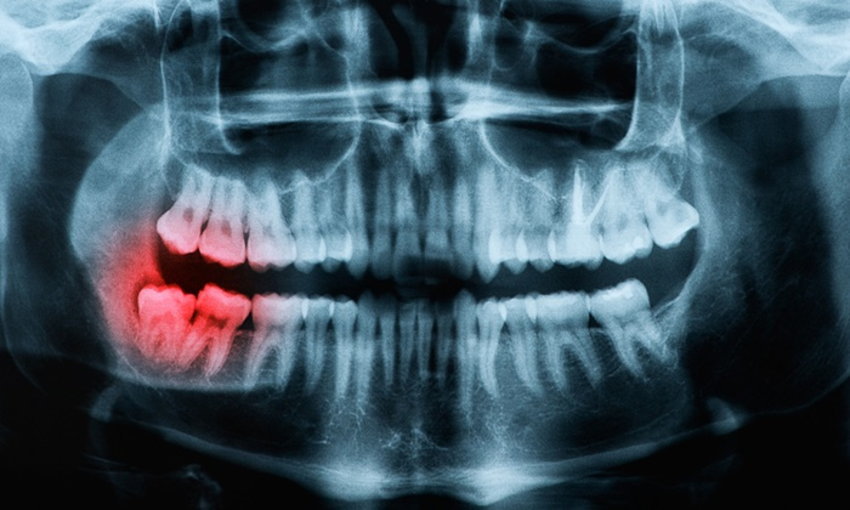

ถ้าไม่ถอน "ฟันคุด" เราจะต้องดูแลและรักษามันอย่างไร ?

เป็นเรื่องปกติสำหรับการมีฟันแท้ที่ขึ้นครบตามจำนวนฟัน 32 ซี่ คนที่กังวลว่า มีฟันคุดหรือเริ่มมีอาการเจ็บ และโดยเฉพาะ คนที่กำลังจะต้องจัดฟัน จะทำอย่างไรเมื่อเราอยากเก็บมันไว้แทนการถอนออก

การถอนฟันคุด หรือผ่าฟันคุด จะขึ้นอยู่กับการประเมินของทันตแพทย์ โดยหากทันตแพทย์ประเมินว่าฟันคุดโผล่ออกมามากพอที่เครื่องมือถอนฟันจะเอาฟันคุดออกได้ ก็จะให้ทำการถอนฟันคุด วิธีนี้จะราคาถูกกว่าการผ่า อย่างไรก็ตาม ค่าถอนฟันคุดยังขึ้นอยู่กับระดับความยากในการถอนฟันคุดด้วย

กรณีที่ต้องผ่าฟันคุดเกิดจากฟันคุดอยู่ลึกลงไปใต้เนื้อเยื่อของเหงือก หรือฟันงอกขึ้นมาบางส่วนแต่มีลักษณะนอน ไม่ตั้งตรง ไม่สามารถดึงขึ้นมาได้ กรณีนี้ทันตแพทย์มักใช้วิธีผ่าเหงือก และอาจมีการตัดผ่าแบ่งฟันออกเป็นชิ้นเล็กๆ แล้วค่อยคีบนำฟันออกมาจากเบ้าฟัน

ฟันคุดขึ้นเต็มซี่

- ทำให้แนวฟันไม่สวยงาม ทำความสะอาดยาก ถ้ามีฟันคุดลักษณะนี้ โดยปกติแล้วก็มักจะรักษาโดยการถอนฟันคุดออก ก็ถือว่าเป็นการรักษาที่เพียงพอ

ฟันคุดแบบมีเหงือกปกคลุม

- ต้องผ่าตัดเอาฟันคุดออกและเย็บแผล อาการไม่ได้น่ากลัวมากนัก เพราะฟันคุดใกล้จะขึ้นแล้ว แต่ถ้าไม่ปวดรุนแรง ก็สามารถรอให้ฟันคุดขึ้นเต็มที่ก่อนได้